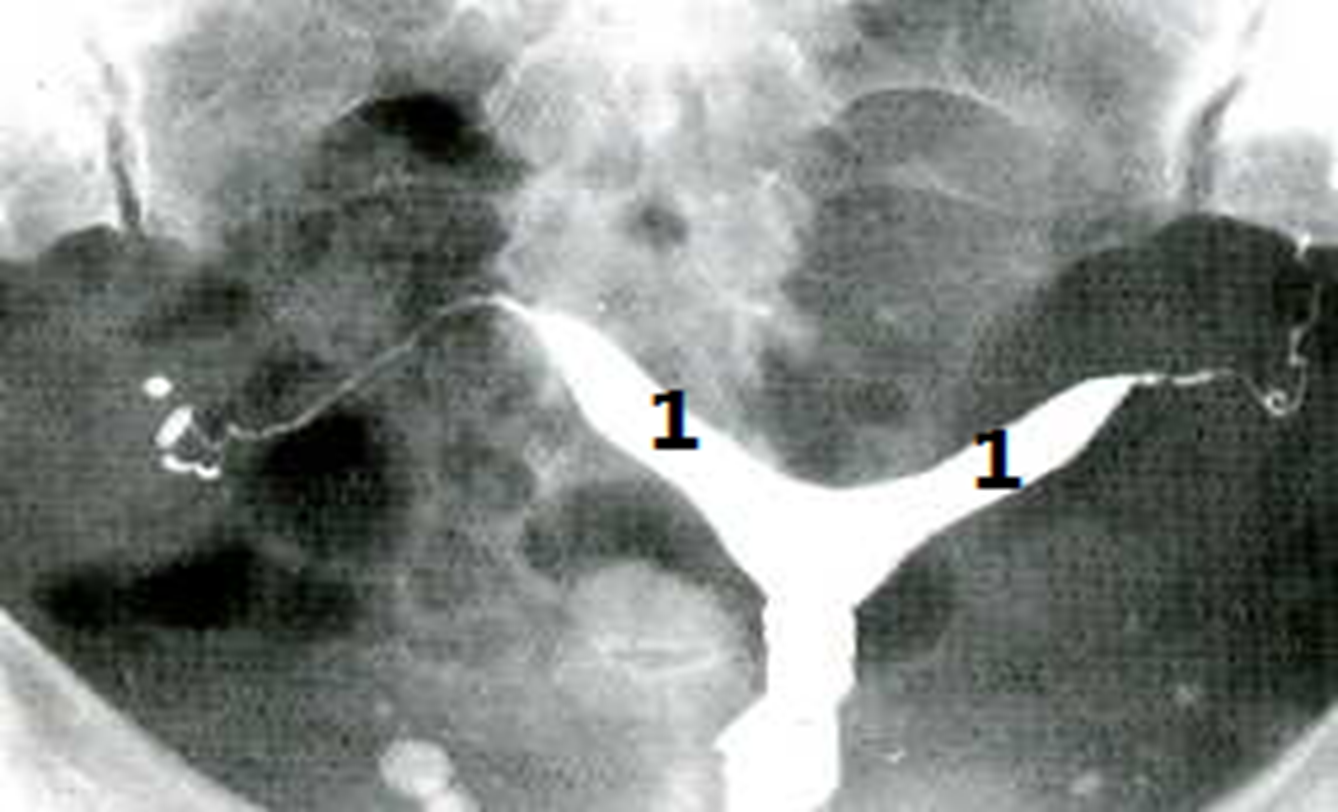

Hysterosalpingogram

A divided uterus can be seen. and an angle between the uterine horns of more than 105° is more consistent with bicornuate uteri.